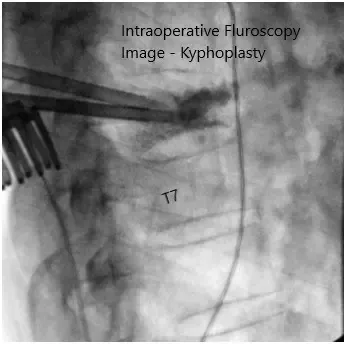

Imágenes de fluoroscopia intraoperatoria.

Volvimos a emplear fluoroscopia para comprobar nuestro nivel de funcionamiento y extendimos ligeramente la incisión en la dirección cefalada. En ese momento, confirmamos el nivel del cuerpo vertebral T6 y comenzamos la cifoplastia abierta.

Primero insertamos las agujas de Jamshidi bajo fluoroscopia a través de los pedículos hasta el cuerpo vertebral. Luego insertamos bilateralmente las cánulas para el sistema de cifoplastia y obtuvimos biopsias transpediculares, que se enviaron a histopatología.

En ese momento, insertamos el balón en el lado derecho del paciente e inflamos con contraste hasta aproximadamente 380 mmHg, comprobando esto constantemente con AP y fluoroscopia lateral simultáneamente. Inflamos el globo hasta aproximadamente 2 mL manteniendo la presión y asegurándonos de mantenernos dentro de los límites del cuerpo vertebral con el inflado del globo.